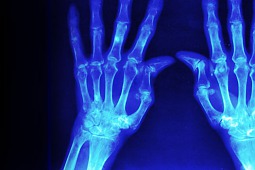

Światowy dzień reumatyzmu

Z tej okazji na portalu społecznościowym Facebook ruszyła akcja pod hasłem rzsporozmawiajmy. Jej celem jest zwiększenie świadomości społeczeństwa na temat reumatoidalnego zapalenia stawów (RZS), którego szczyt zachorowalności przypada na 30 – 40 r.ż., zachęcenie do wykonywania badań diagnostycznych w kierunku RZS oraz zwrócenie uwagi na problem nieprzestrzegania zaleceń terapeutycznych przez pacjentów chorych na RZS.

Reumatoidalne zapalenie stawów